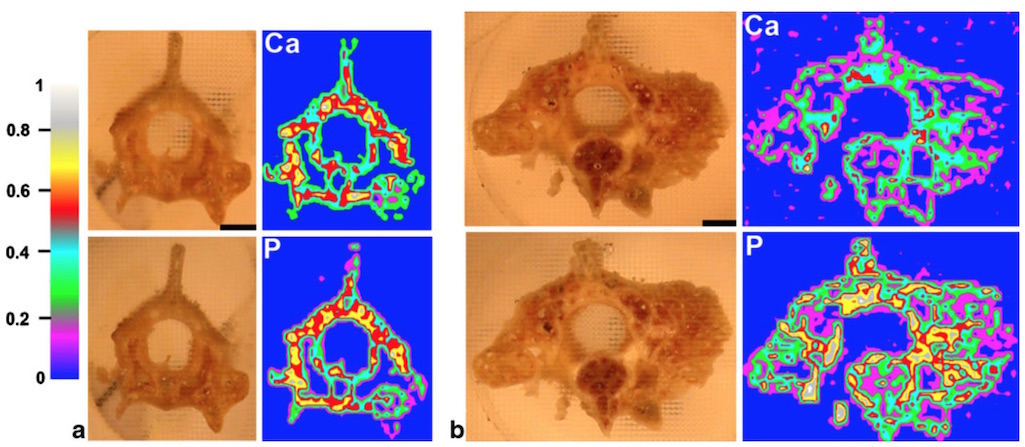

In 2010, the laser spectroscopy laboratory represented by Kaiser used LIBS technology combined with μCT technology to study and analyze the distribution of spine bone elements including Ca, Al, P, Na, etc. of snake deformity osteitis, and published "Investigation of The osteitisdeformans phases in snake vertebrae by double-pulse laser-induced breakdown spectroscopy" (Anal. Bioanal. Chem. 398:1095-1107, 2010)

The picture above shows the snake spine μCT, the picture below shows the snake's normal vertebrae (a) and pathological vertebrae (b) two-dimensional distribution of calcium and phosphorus.